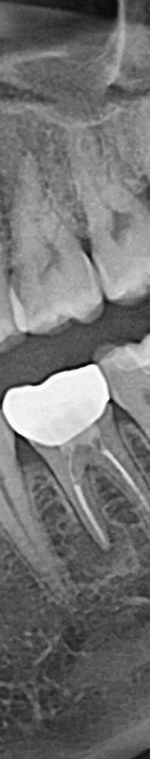

사랑니발치를 하기 위해서는 먼저 파노라마 x선 사진을 통해 발치 시 신경에 영향을 줄 수 있는지 확인하는 과정을 진행했어요. 이 과정을 통해서 충분히 의사와 상담을 한 후 처방전을 발급했어요. 이 때 처방전에는 항생제를 포함하여 발치 후 통증을 대비한 진통제를 처방했어요. 환자에게 충분히 설명한 후에 국소마취를 진행하고 마취가 된 다음에 절개를 최대한 덜 하는 방향으로 수술하여 사랑니를 발치했어요.

사랑니가 90도로 누워서 난 경우는 수평 매복, 뼈나 잇몸에 사랑니가 완전히 덮여서 아예 보이지 않는 경우는 완전 매복, 일부분만 잇몸이나 뼈에 덮여있는 경우 부분매복이라고 했어요. 대부분의 환자분이 이런 매복 중에 한 가지에 해당하기 때문에 시술이 매우 어려웠어요. 특히 사랑니 주변으로는 구강과 관련된 중요한 신경 조직이 인접하여 있기 때문에 고난이도 시술이라고 할 수 있었어요.

매복이든 잠복이든 잇몸을 절개하여 치아를 꺼내는 방법으로 수술을 진행했어요. 이 때 필요에 따라서 치아를 부수거나 조각을 내서 제거해야 할 수도 있었어요. 발치가 끝나면 절개한 잇몸을 봉합하고 소독을 한 후에 회복을 위해 필요한 안내 사항 및 주의 사항을 전달했어요. 발치를 한 다음 날 다시 내원하여 상태를 살펴보고 소독하게 되었어요. 수술로 발치를 했을 경우에는 일주일 후 다시 내원하여 실밥을 제거하는 과정을 진행했었어요.